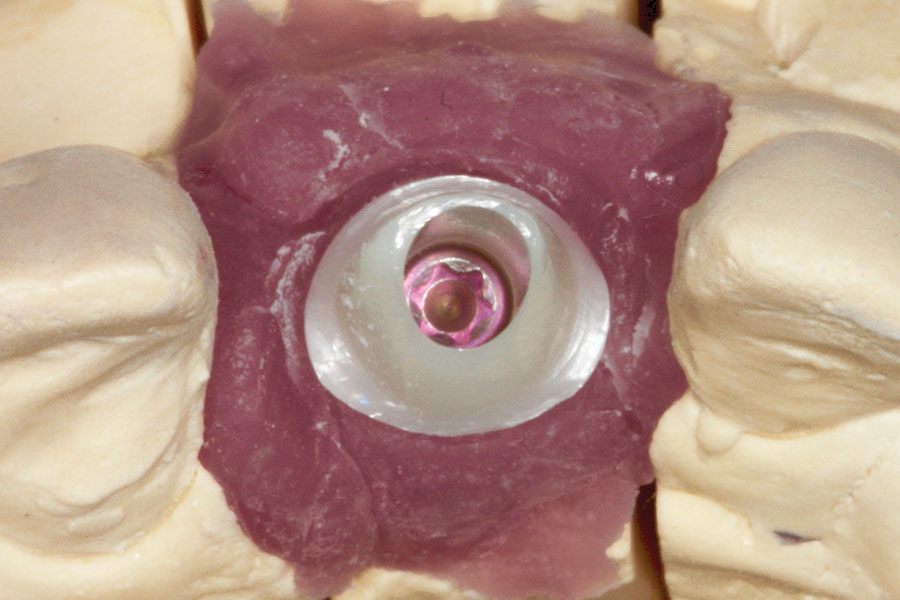

Dentsply Sirona’s integrated solutions for implant dentistry enable dental professionals to deliver safer and more efficient treatment processes as well as increased comfort and improved quality of life for their patients. The merger between DENTSPLY and Sirona has brought together two companies with long-term expertise in their respective fields, providing innovative and clinically tested technology, … Read more